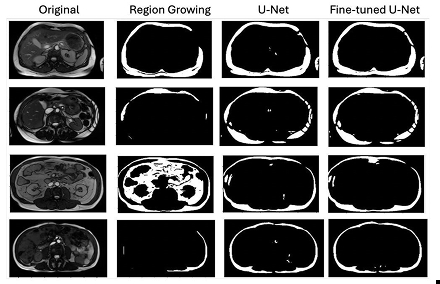

Table 1 summarizes the mean clinical evaluation scores across all patients and metrics. The UNet and Fine-Tuned UNet consistently outperformed Region Growing in all four metrics, with mean accuracy of 2.81 and 2.80, respectively, versus 2.16 for Region Growing. Figure 1 shows example segmentations for each method. Figures 2 and 3 visualize model performance, highlighting mean scores in complex cases and the percentage of perfect (3/3) segmentations. The Fine-Tuned UNet had the highest mean accuracy (2.80) in challenging images, while the base UNet had the most perfect scores overall (73.3%).